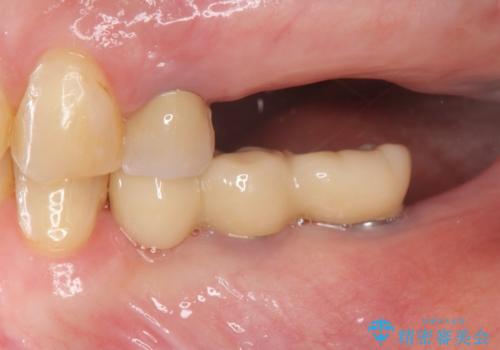

- 奥歯を虫歯で失ってしまい、しっかりと噛めるようになりたい、と希望され来院されました。

3本の歯(クラウン)を2本のインプラントで支えるインプラントブリッジによる咬合機能の回復を計画します。

治療後、しっかりと咬合機能が回復され見た目の自然さにも満足いただくことができました。